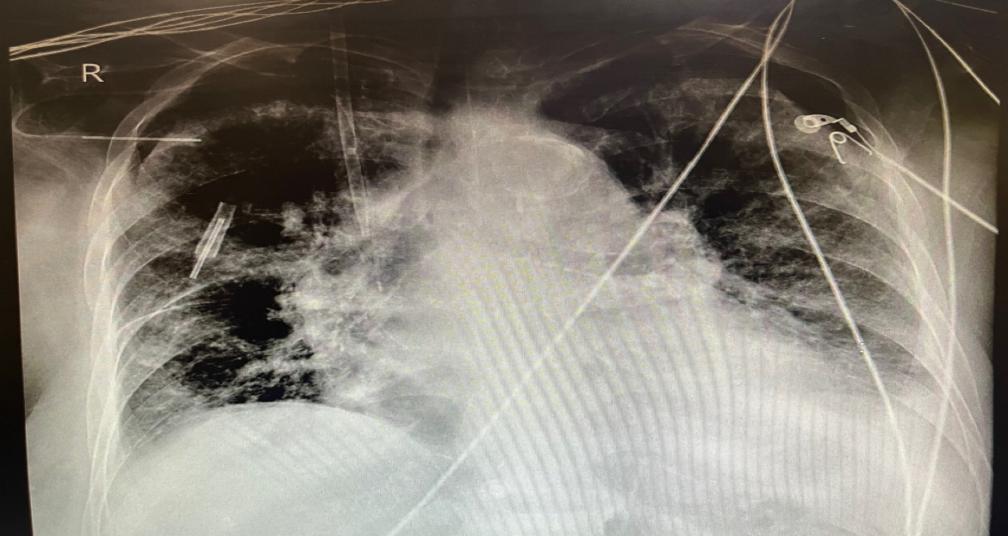

手术由急诊高级实践护士(APN)方鹏主责,静疗门诊小组长张霞飞协助。术中采用超声精准定位,在右侧胸壁段腋静脉最佳穿刺点(胸小肌上缘至第一肋之间)实施穿刺。置管过程中,通过腔内心电图定位技术实时监测导管位置,并根据P波幅值调整导管尖端位置,最终将导管末端安全留置于上腔静脉中下1/3处。整个操作过程平稳,患者生命体征稳定,术中出血量少,一次性完成置管。